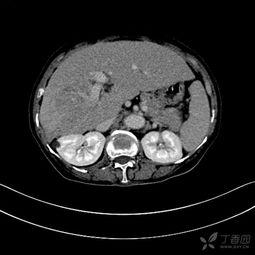

首先,得先弄清楚什么是胆管细胞癌。胆管细胞癌,顾名思义,就是发生在胆管上的恶性肿瘤。胆管是连接肝脏和胆囊的管道,负责将胆汁输送到小肠。当胆管细胞发生癌变时,就会形成胆管细胞癌。